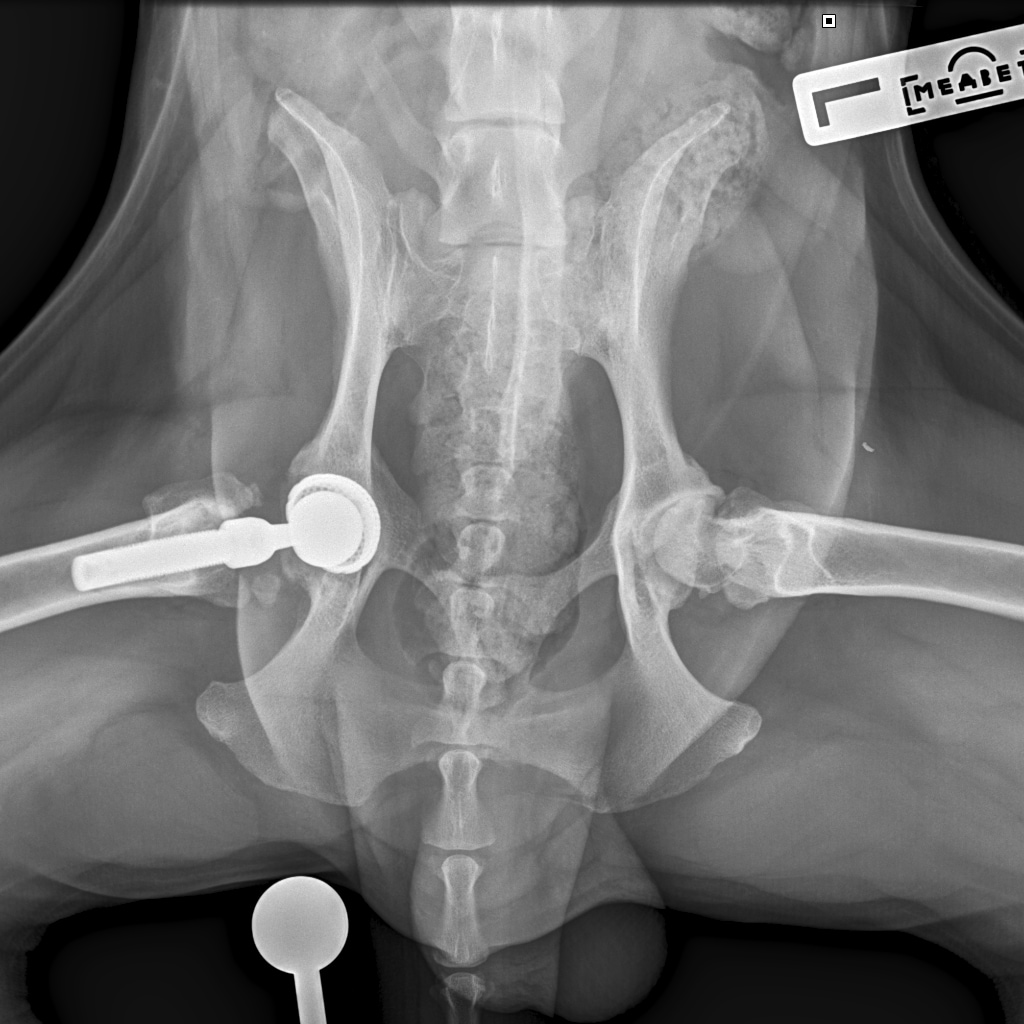

Съездили мы с Бруно к врачу. Скажу честно, и врач очень расстроился, увидев состояние шва, и мы с Ирой вслед за врачом. Илья Федорович очень опасался, что свищ дошел до сустава, а это самое плохое осложнение, которое можно себе представить. Забрали Бруняшу, сделали наркоз, рентген под наркозом, всё вычистили, наложили швы. По словам хирурга, внешне пока до сустава не дошло, воспалительный процесс, вызванный разлизанным швом и попаданием туда инфекции, затронул только мягкие ткани. Но бакпосев взяли. Будет готов через 5-10 дней. Ждем и надеемся. А пока продолжаем пить антибиотики, обрабатывать дренаж, который вставили в шов во время операции сегодня, беречь шов как зеницу ока.

Присмотрелась к числам, а мне дважды прислали после операционный:(((

Запросила ещё и вот:((((

Все не здорово....